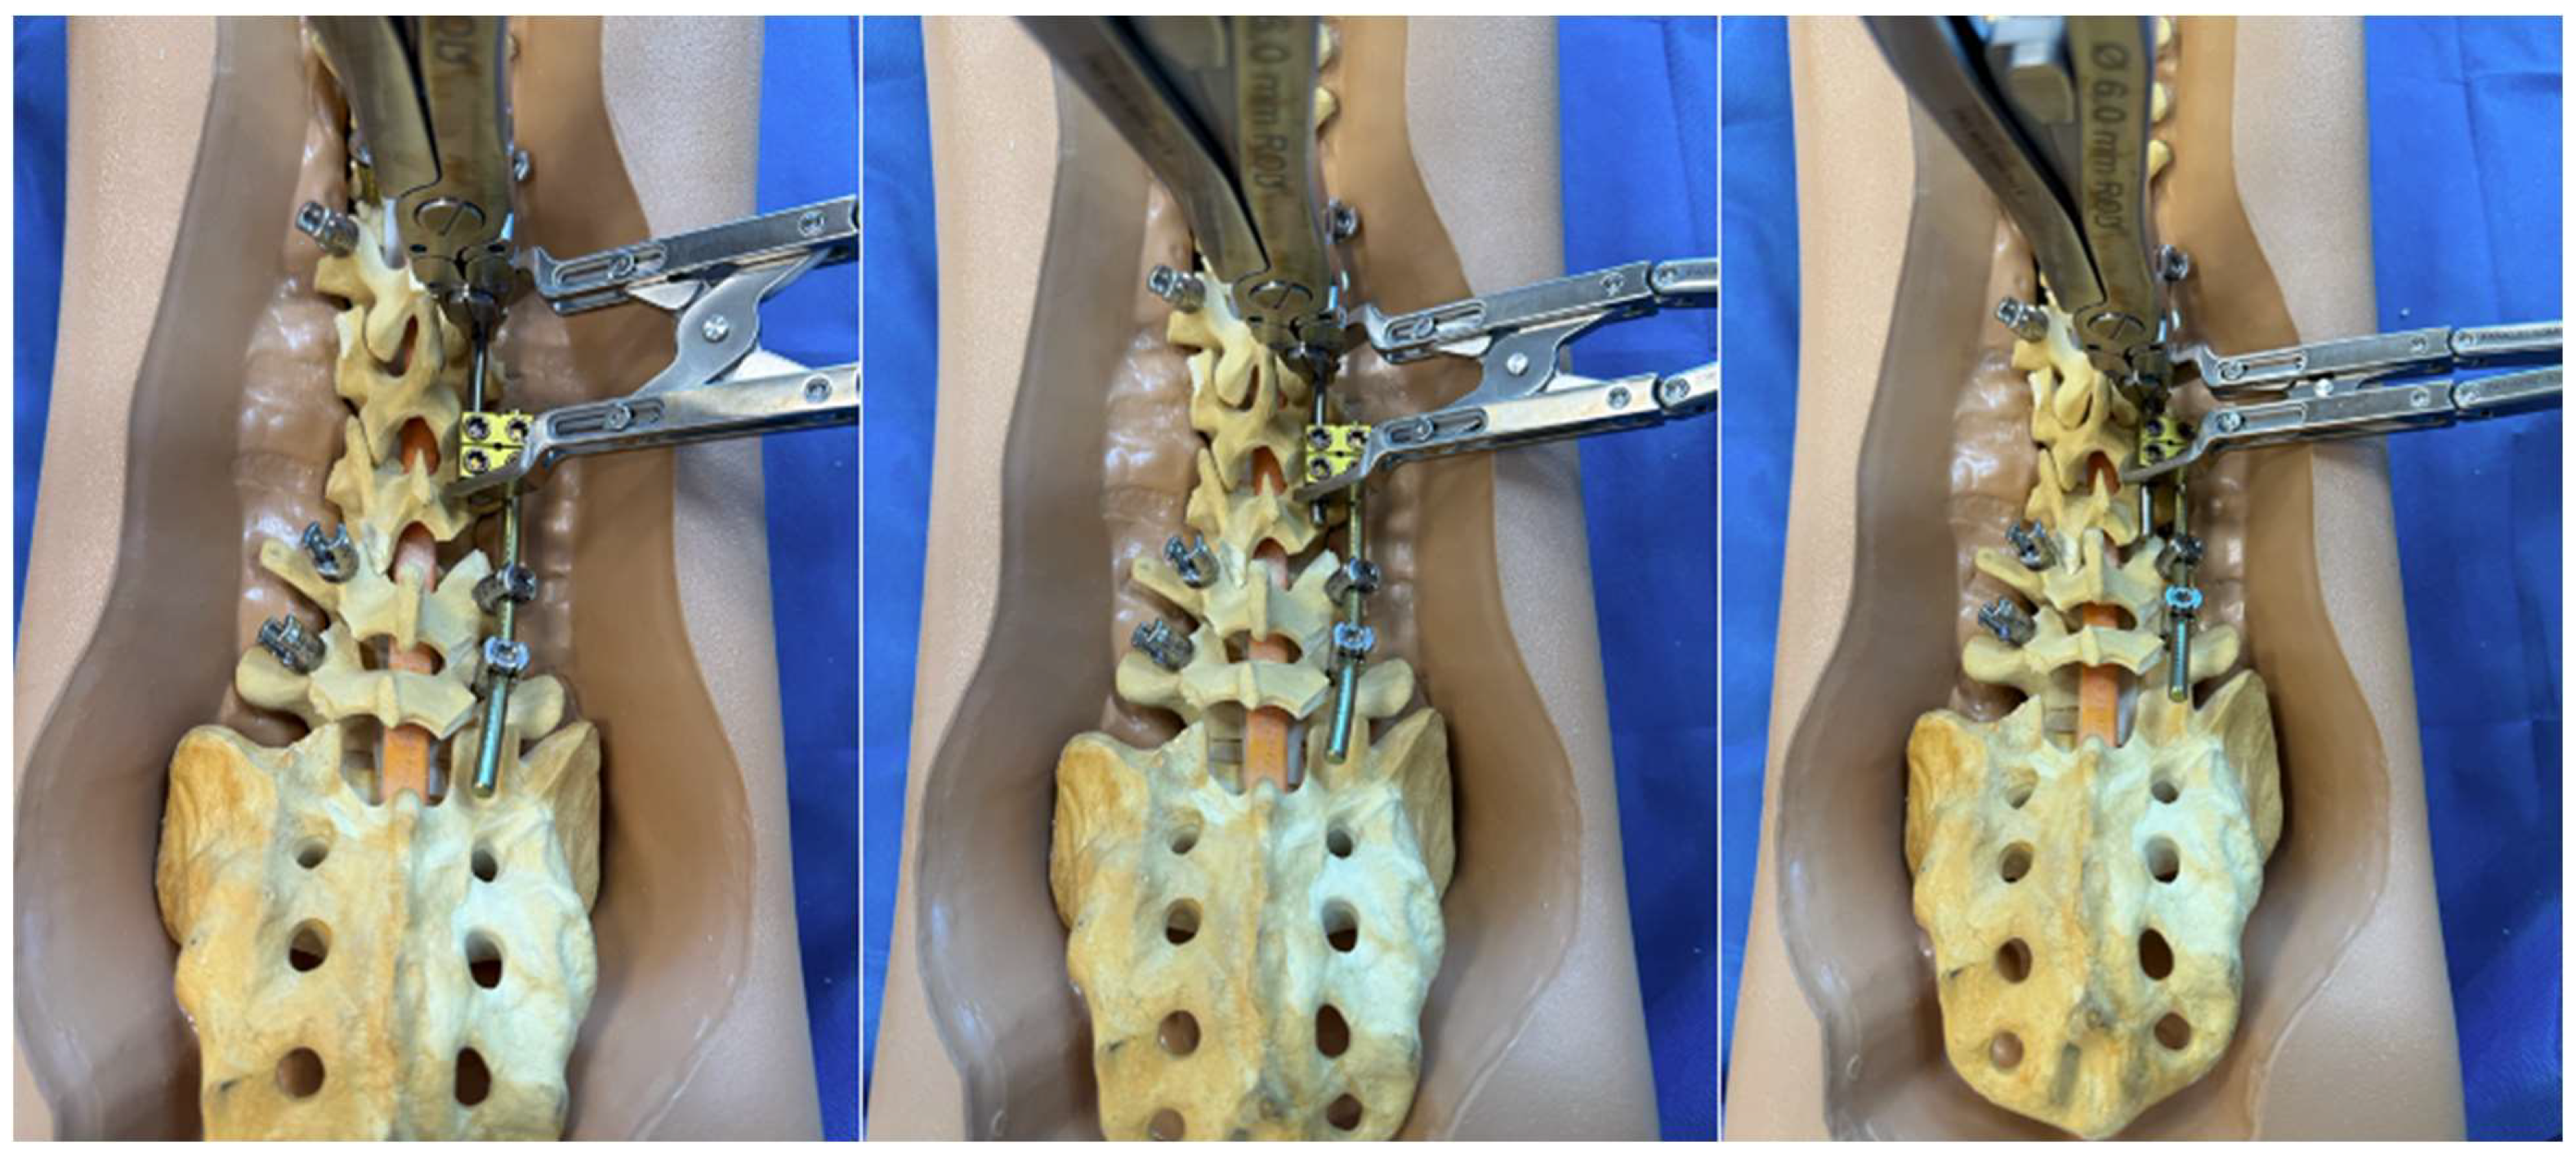

3.2. Internal Distraction on the Concavity of a Major Scoliosis Curve

The first clinical scenario where the construct-to-construct internal distraction technique may be useful is during surgical correction of severe scoliosis curves > 90 degrees. This technique is most effective in large, flexible sweeping curves that involve multiple spinal levels. Sharply angulated and rigid curves with high-deformity angular ratios (DAR) are better managed with three-column osteotomies [5,6]. We prefer placing our anchor points to set up the construct-to-construct internal distraction configuration early in the procedure. The viscoelastic environment of the spine will permit gradual sequential distraction to relax soft tissues and make them more compliant with progressive correction techniques. In severe major curves, it is often challenging to get the rods parallel into the domino connectors. A combination of rod bending and handling with a rod gripper helps achieve the contour necessary to set up the construct-to-construct configuration. After initial distraction is performed on the concavity of the scoliosis (Figure 3), the remainder of the spine should be exposed in a subperiosteal manner. Posterior column osteotomy releases will gradually enhance deformity correction by removing the posterior spinal elements, so long as the anterior columns of the corresponding motion segments are not fused together. Small and repetitive distraction maneuvers are applied over the course of the surgery until appropriate correction is achieved and final fusion may be performed. Upgoing rib hooks sometimes provide an excellent option for internal distraction (Figure 4 and Figure 5). If adequate correction is not achieved or there is concern about risk of neurological injury due to intraoperative neuromonitoring (IONM) changes, then a staged procedure may be performed at a later time.

Figure 3.

Step-by-step schematic of the construct-to-construct internal distraction technique. The green caps represent loose set caps. Red caps represent tight set caps.

3.3. Traditional Growing Rods

The construct-to-construct internal distraction technique is the most common configuration for traditional growing rod constructs (Figure 6). The distal anchor points comprise two-level pedicle screw fixation. The last spinal level will represent the lower instrumented vertebra of the final fusion construct. The proximal anchor points may be either upgoing rib hooks or pedicle screws. We prefer pedicle screw fixation at upper instrumented vertebra, upper instrumented vertebra-1, and occasionally upper instrumented vertebra-2. It is important to keep in mind that these proximal pedicle screws will experience significant distraction forces with serial lengthening that could loosen the screws at the time of the final spinal fusion. A long titanium rod is passed under the muscle layer to engage into the proximal anchor points. The distal segment of this rod is connected to a lateral domino connector with significant overlap to allow for serial distraction in the future. A shorter rod is tunneled through the domino connector and engaged to the distal anchor points. A rod gripper is used to engage the longer, proximal rod approximately 1 cm above the domino connector (Figure 3). The set cap on the domino connector is loosened, and a distractor is placed between this connector and the rod gripper. Gradual distraction is applied in a controlled, “click-by-click” manner before the set cap is tightened to hold the correction.

Figure 6.